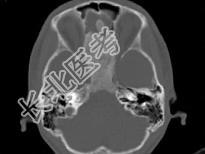

- 单项选择题女,17岁, 鼻阻塞、头痛两年.如图所示符合筛骨病变最可能的诊断是 ( )

B、纤维异常增殖症

E、骨化性纤维瘤